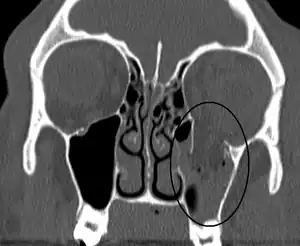

| Blowout fracture | |

|---|---|

| Other names | Orbital floor fracture |

| An orbital blowout fracture of the floor of the left orbit. | |